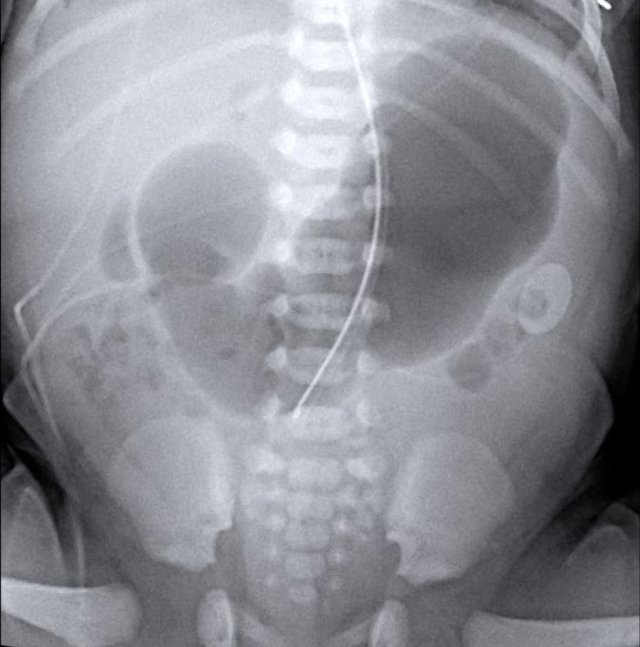

Radiographs will show multiple dilated bowel loops and absence of air in the colon as seen on the image on the left.

A colon enema will show a microcolon with contrast filling ending blind in the ileum (arrow on image on the right).